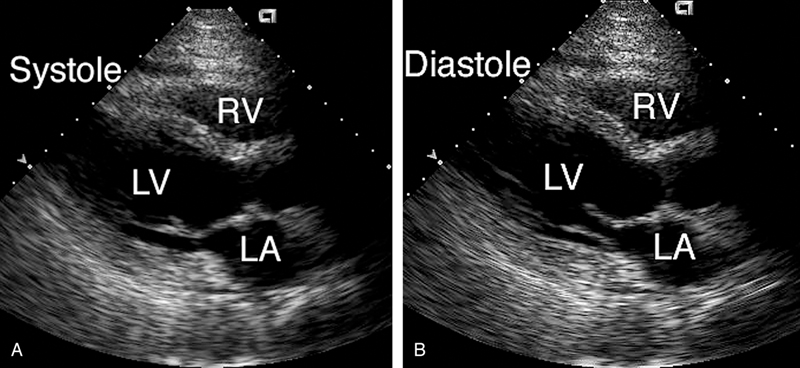

فحوصات تشخيصية لبعض امراض القلب والشرايين التاجية